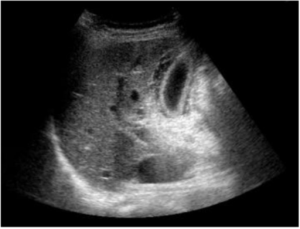

- Biliary ultrasound

- Gallstones

- Distinguish by characteristic "shadowing"

- Better seen with patient in left lateral decub

- GB wall thickening (>3mm)

- May also be seen with Pancreatitis, ascites, Congestive heart failure, alcoholic hepatitis

- Pericholecystic fluid

- Sonographic Murphy's Sign (PPV 92%)

- May be absent in patients with DM, gangrenous cholecystitis